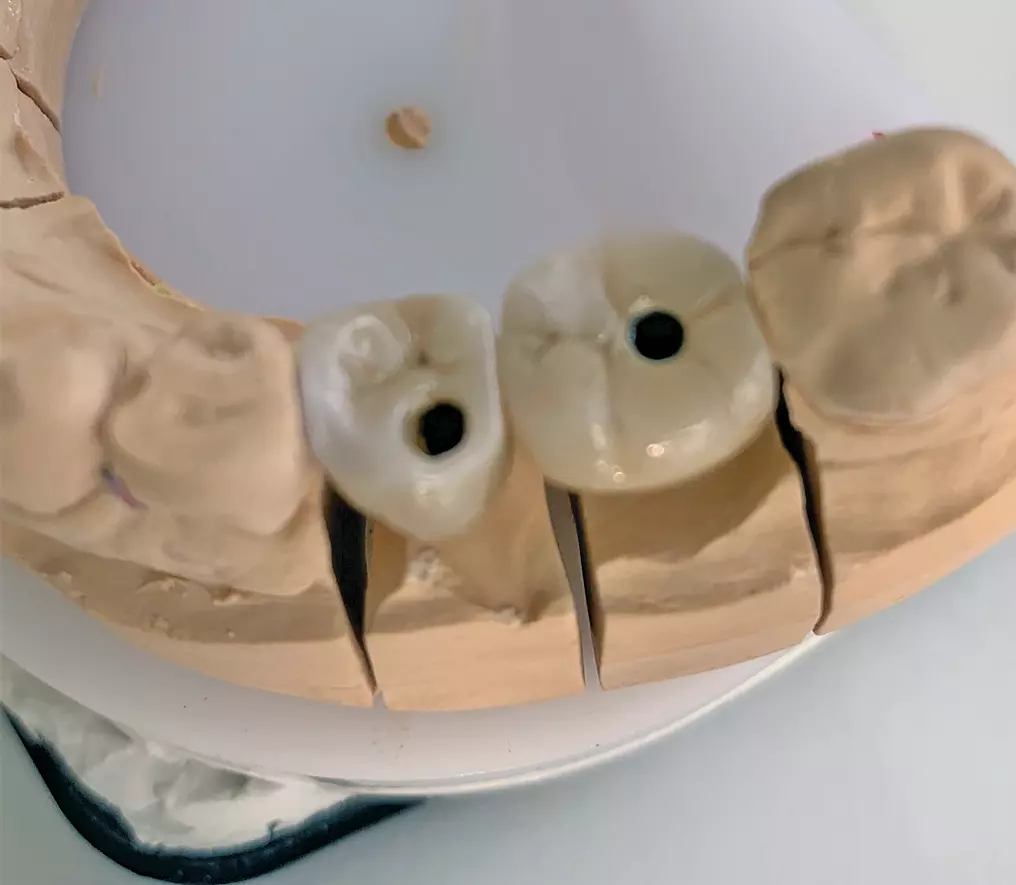

Verschraubung der mit dem Abutment verklebten Restauration direkt im Implantat

Ein weiterer Vorteil ist darin zu sehen, dass nur eine Verschraubungseinheit vorliegt, deren Schraubenkopf zudem tief an der Basis des Abutments angeordnet ist und einen relativ kleinen Durchmesser aufweist. Damit lässt sich der okklusale Zugang in gleicher Weise wie oben erwähnt verschließen und ein günstiger kosmetischer Effekt erzielen (Abb. 5a-d).